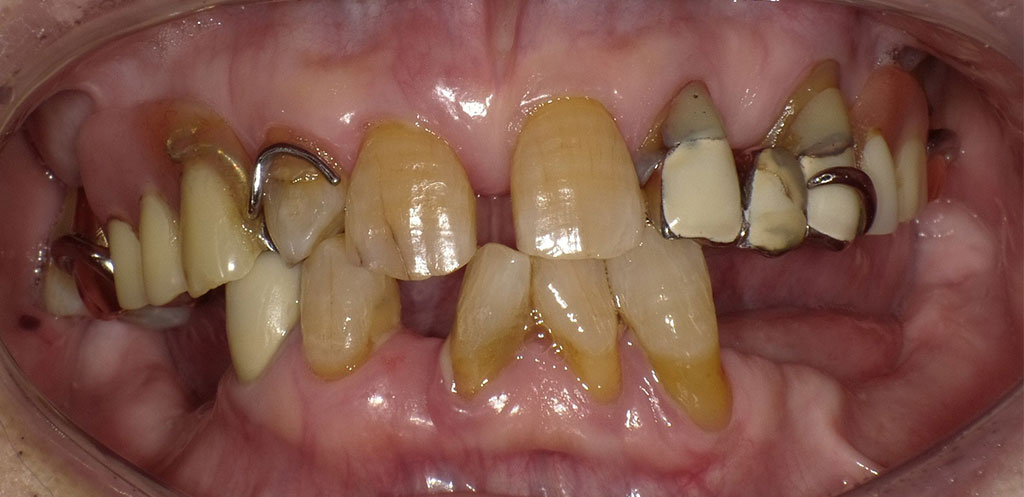

Before2

After2

治療内容

金属部分が目立たない、フィット感がある、入れ歯を支える歯への負担を軽減させるため、下顎左7652番および右14567番が欠損を補う自費の入れ歯を作成。異物感をできるだけ少なくするために、オールプラスチックのスマイルデンチャーは選択せず、舌で触れる部分はメタルで薄く加工することにした。またクラスプも金属のため、緩くなったら締めなおせるというメリットもある。デジタルスキャナーで型取りをして、3Dプリンターで模型を作成し、その精密な顎模型を製作。そして当院専属の入れ歯技工士早澤が入れ歯を精魂込めて製作いたしました。